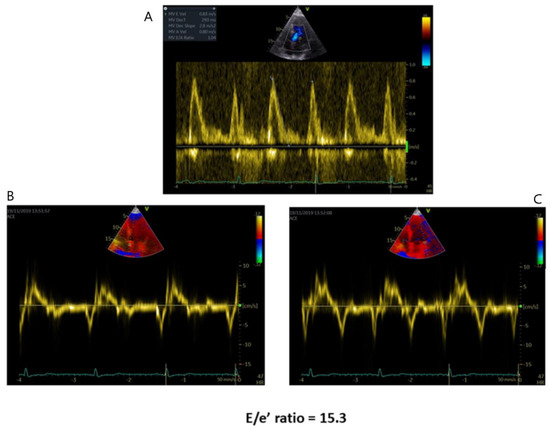

2.2. Left Ventricular Diastolic Function

- Palecek, T.; Linhart, A.; Lubanda, J.C.; Magage, S.; Karetova, D.; Bultas, J.; Aschermann, M. Early diastolic mitral annular velocity and color M-mode flow propagation velocity in the evaluation of left ventricular diastolic function in patients with Fabry disease. Heart Vessels. 2006, 21, 13–19. [Google Scholar] [CrossRef]

- Pieroni, M.; Chimenti, C.; Ricci, R.; Sale, P.; Russo, M.A.; Frustaci, A. Early detection of Fabry cardiomyopathy by tissue Doppler imaging. Circulation 2003, 107, 1978–1984. [Google Scholar] [CrossRef] [PubMed]

- Zamorano, J.; Serra, V.; Pérez de Isla, L.; Feltes, G.; Calli, A.; Barbado, F.J.; Torras, J.; Hernandez, S.; Herrera, J.; Herrero, J.A.; et al. Usefulness of tissue Doppler on early detection of cardiac disease in Fabry patients and potential role of enzyme replacement therapy (ERT) for avoiding progression of disease. Eur. J. Echocardiogr. 2011, 12, 671–677. [Google Scholar] [CrossRef]

- Liu, D.; Oder, D.; Salinger, T.; Hu, K.; Müntze, J.; Weidemann, F.; Herrmann, S.; Ertl, G.; Wanner, C.; Frantz, S.; et al. Association and diagnostic utility of diastolic dysfunction and myocardial fibrosis in patients with Fabry disease. Open Heart 2018, 5, e000803. [Google Scholar] [CrossRef] [PubMed]

| Diastolic Dysfunction | -Mitral flow Doppler parameters alteration -E/e’ ratio increase -LA dilation | -In AFD patients with LV hypertrophy, diastolic dysfunction underlies the symptoms of heart failure |